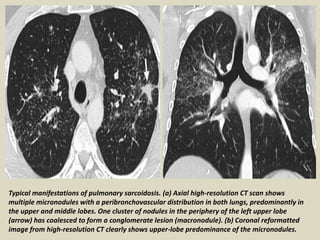

Typical manifestations of pulmonary sarcoidosis. (a) Axial high-resolution CT scan shows

multiple micronodules with a peribronchovascular distribution in both lungs, predominantly in

the upper and middle lobes. One cluster of nodules in the periphery of the left upper lobe

(arrow) has coalesced to form a conglomerate lesion (macronodule). (b) Coronal reformatted

image from high-resolution CT clearly shows upper-lobe predominance of the micronodules.